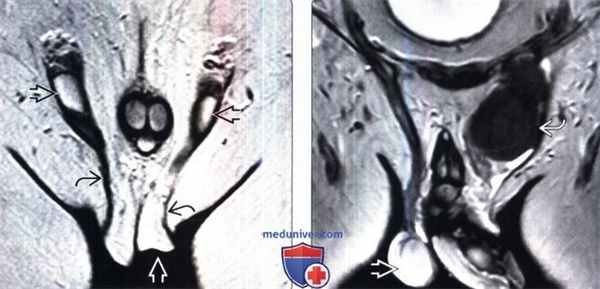

• Отсутствие семенного канатика в паховом канале 4. МРТ при крипторхизме:

• Т1-ВИ: гипоинтенсивное овоидное образование

• Т2-ВИ: гиперинтенсивное овоидное образование, но зачастую не такое светлое, как нормальные яички:

о Снижение интенсивности сигнала на Т2 вследствие фиброзных изменений

о Очаговое уменьшение интенсивности сигнала на Т2 позволяет заподозрить наличие опухоли

(Слева) МРТ, Т2-ВИ, корональный срез: пустая мошонка и неопущенные яички с двух сторон. Отчетливо определяется губернакулум — связка, распространяющая от нижнего полюса яичка до мошоночного мешка.

(Справа) МРТ, Т2-ВИ, корональный срез: гипоинтенсивная опухоль в неопущенном яичке. Сравните этот сигнал с нормальным опустившимся яичком справа. Важно знать, что возросшему риску возникновения рака подвергается не только неопущенная сторона, но и здоровое опустившееся яичко.